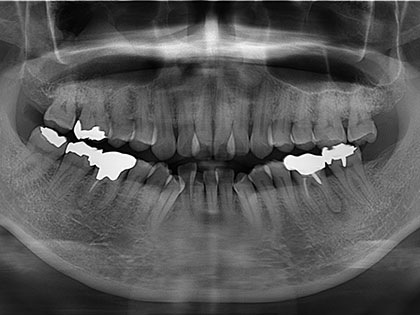

右上歯が欠け、インプラント治療を希望された患者様の症例になります

右上歯が欠け、インプランを希望との事で来院

• 右上歯が欠けた、ぐらぐらする歯肉の奥深くまで割れていることにより抜歯